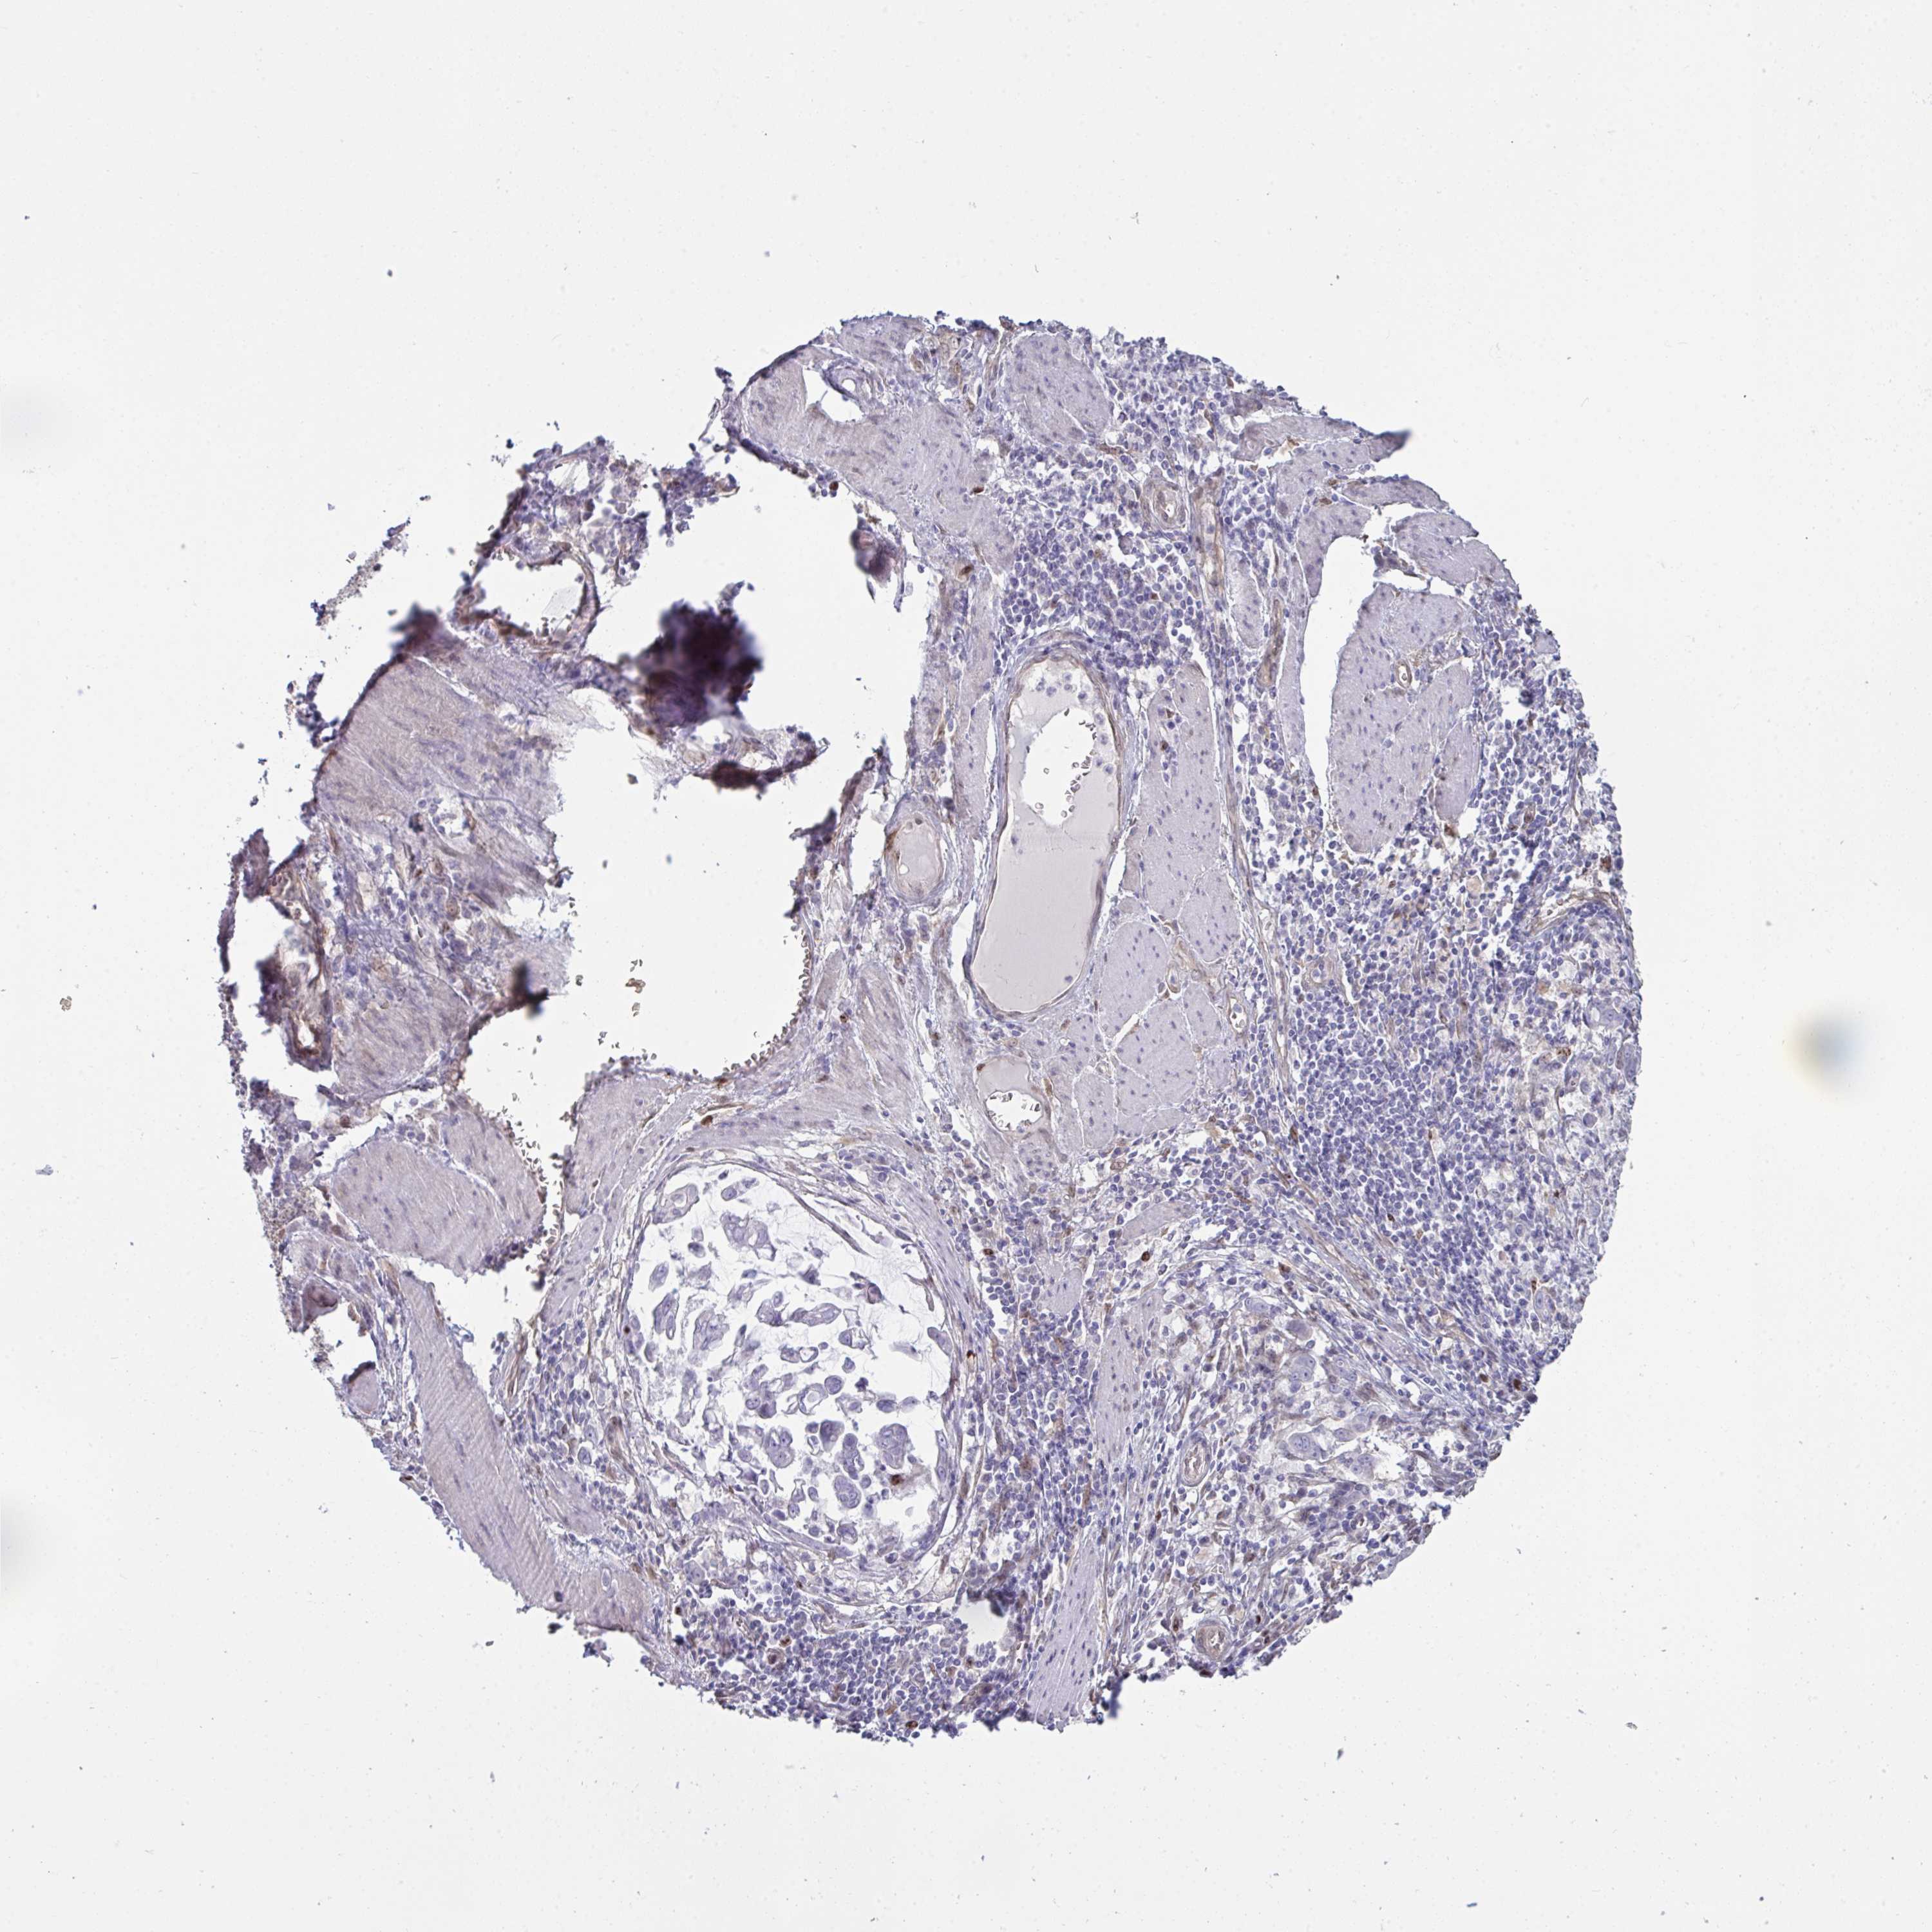

STOMACH CANCER - Protein expressioni

A mouse-over function shows sample information and annotation data. Click on an image to view it in a full screen mode. Samples can be filtered based on level of antibody staining by selecting one or several of the following categories: high, medium, low and not detected. The assay and annotation is described here.

Antibody stainingi

Antibody staining in the annotated cell types in the current human tissue is reported as not detected, low, medium, or high, based on conventional immunohistochemistry profiling in selected tissues. This score is based on the combination of the staining intensity and fraction of stained cells.

Each image is clickable and will lead to virtual microscopy that enables deeper exploration of all samples and also displays staining intensity scores, fraction scores and subcellular localization as well as patient and tissue information for each sample.

Antibody HPA058111

Staining

High

Medium

Low

Not detected

Intensity

Strong

Moderate

Weak

Negative

Quantity

>75%

75%-25%

<25%

None

Location

Nuclear

Cytoplasmic/membranous

Cytoplasmic/membranous,nuclear

Adenocarcinoma, NOS